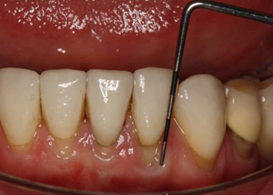

The probe should be inserted parallel to the root surface into the periodontal pocket and ‘walked’ around the gingival margin (see figure: "Walking the probe). Probing depth should be measured at six sites per tooth.

A PCP 12 probe is ‘walked’ around the gingival margin of the tooth.